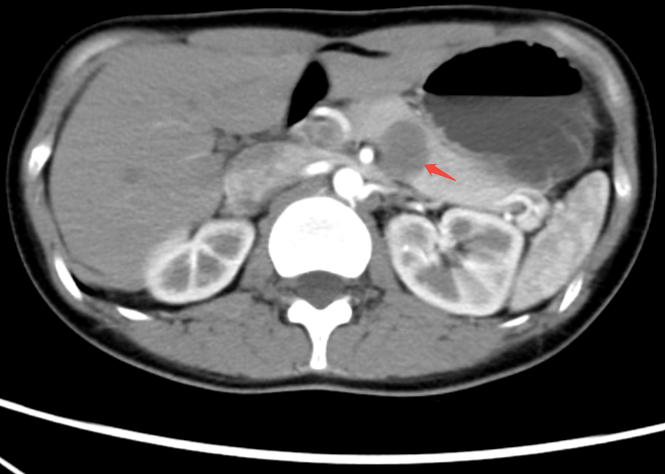

此次手术采用了最新的微创技术,通过 3D 腹腔镜系统辅助,实现了对肿瘤的精准切除。与传统手术相比,这种新技术具有创伤小、恢复快、并发症少等显著优势。手术过程中,两个团队的医生通过高分辨率的三维影像系统,精确控制手术器械,以最小的侵入性完成肿瘤的切除,极大地降低了手术风险。

患者罗女士(化名)便是此次手术的受益者。被确诊为胰腺肿瘤后,罗女士一度陷入绝望,尚未婚配的她对肿瘤切除后的生活质量及伤口疤痕有着极高要求。为满足患者需求,南方科技大学医院肝胆胰外科与北大医院医疗团队多次深入研讨,最终为罗女士量身定制了一套详细的微创手术方案。

手术如期顺利实施,罗女士的胰腺肿瘤被成功切除,近邻脾脏也得以完整保留,术后伤口疤痕极小,恢复期明显缩短。